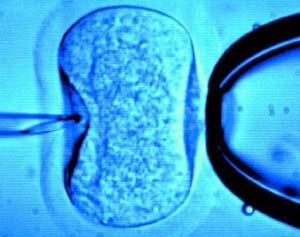

Fecundação in vitro (FIV)

Esta técnica, também denominada “bebé-proveta”, foi uma das grandes conquistas no tratamento da fertilidade.

Em que consiste a FIV?

Fig. 1 – Fecundação in vitro

A FIV é um processo que envolve vários passos complexos:

A mulher é submetida a um tratamento com medicamentos que permitem a indução da ovulação, ministrados por via injectável. Tais medicamentos vão estimular os ovários a produzirem mais oócitos do que é habitual.

Quando o médico verifica que os folículos já estão suficientemente desenvolvidos e contêm um folículo maduro, é administrada uma injecção de HCG (Gonadotropina Coriónica Humana) cuja função é provocar a libertação dos oócitos para os ovidutos.

Nesta fase o tempo tem um papel fundamental pois a punção2 deverá ser realizada 35 a 36 horas após a administração de HCG. Por isso é muito importante que o casal respeite as horas indicadas pelo médico para a administração das várias injecções, já que um erro pode pôr em causa todo o processo.

Seguidamente, os seus óvulos e os espermatozóides do parceiro são colocados juntos para serem fecundados. Durante os dias seguintes, os óvulos fecundados iram dividir-se e tornar-se embriões, sendo depois transferidos para o útero da mulher para que se implantem e dêem origem a uma gravidez.

Os embriões excedentários que não foram utilizados podem ser congelados e utilizados num ciclo posterior, ou seja, no caso do casal querer ter um segundo filho ou se a primeira tentativa falhar, cabendo ao casal decidir sobre o seu destino, desde que respeite as condições previstas pela lei.

No fim da implantação, a mulher começa a aplicar progesterona de modo a preparar o endométrio de modo a que a implantação seja bem sucedida.

A taxa de sucesso deste tratamento varia entre os 20 e os 35% em mulheres até aos 35 anos. A partir dos 40 anos esta taxa já diminui para os 15%.